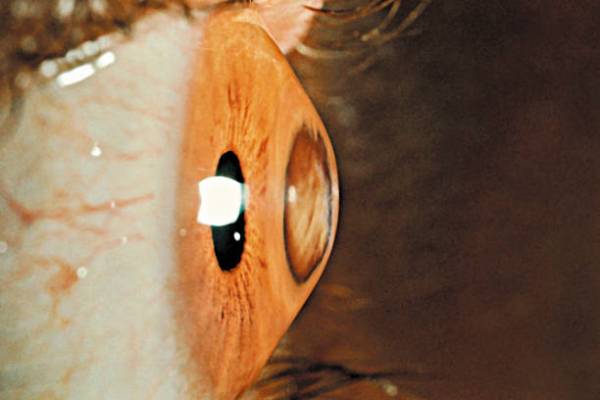

Keratoconus Cross-Linking: Complete Patient Guide

Keratoconus affects the cornea's shape, causing vision problems that worsen over time. This progressive condition creates a cone-like bulge in the eye's front surface. Cross-linking offers hope for patients seeking…